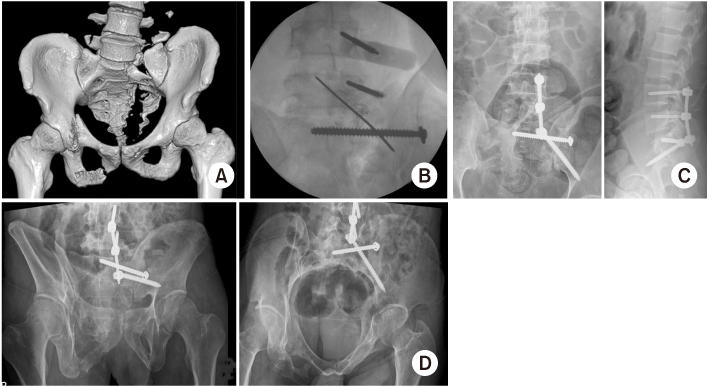

Fig. 10

(A) A 57-year-old male sustained an unstable pelvic injury with L5 body fracture. (B) First, the pedicle screw of L4 and L5 was placed percutaneously and made the entry portal for the S2 alar-iliac (S2AI) screw. (C) The postoperative radiographs showed the functional reduction of the pelvis. (D) Follow-up radiographs at eight weeks showed the maintenance of reduction adequacy.